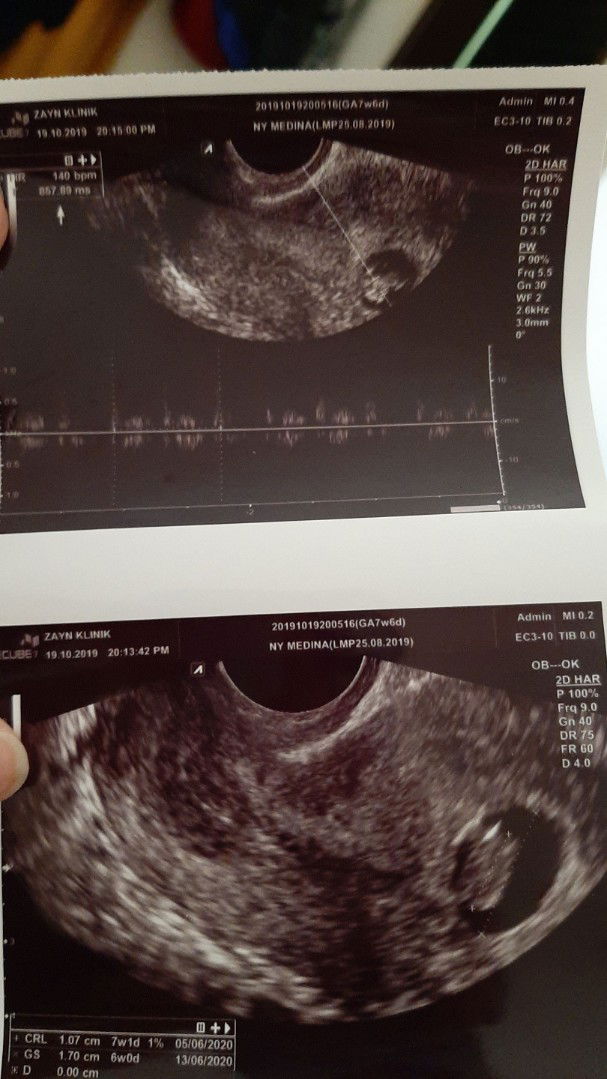

Trnyata banyak bunda2 yg mirip sma kehamilanku Ngeflek diusia kandungan 6w 7w dan sterusnya Alhamdulillah tiap cek & usg ke dokter janin Smuax aman2 & sehat Bahkan bnyak bunda yg hmpir tiap bulan ngeflek tp Alhamdulillah bayi lahir sehat & selamat Mdh2an bsa sprti bunda2 yg lain? Biar gak trllu worry rajin baca2 postingan bunda2 scara tdk lgsg bsa jd pnyemangat & jd gak kebawa stress Ini usg pas 7w kata dokter djj kurang Share donk hasil usg bunda2 & djj